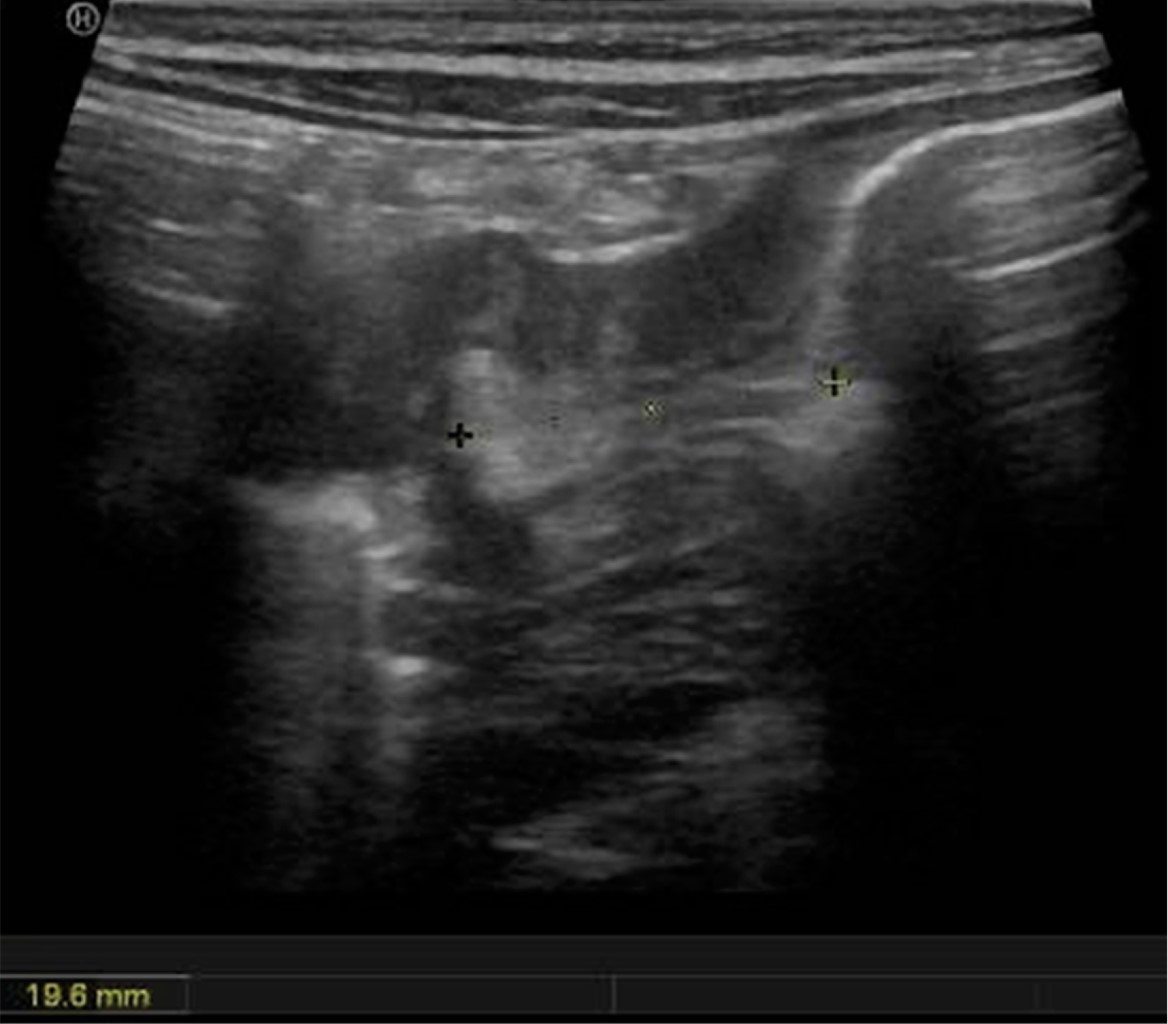

Figure 4